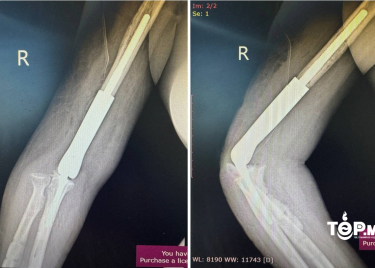

ГССҮТ: Эмч нар тохойн үе, атгаал ясны дутмагшлыг н...